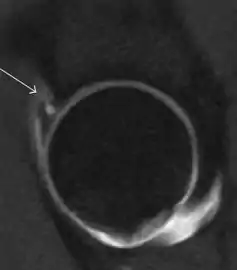

Most of the angles and measurements described in the plain radiograph section can be accurately reproduced on MRI. In addition, the superiority of MRI resolution with intra-articular contrast allows detection of labral and chondral abnormalities that may influence the choice of medical, percutaneous, or surgical management (Figure 9).[1]

Figure 9:

Sagittal T1 weighted image showing chondral lesion.[1]

Sagittal CT-arthrography showing posteroinferior chondral injury.[1]

Coronal CT-arthrography (d) showing ligamentum teres tear.[1]

MR arthrography has proven superior in accuracy when compared to native MR imaging. It is considered the best technique to assess the labrum. Knowledge of the normal variable morphology of the labrum helps to differentiate tears from normal variants. A triangular shape is most commonly seen in 66% of asymptomatic volunteers, but round, flattened, and absent labra can also be found in asymptomatic populations. MR arthrography has demonstrated sensitivity over 90% and specificity close to 100% in detecting labral tears. Loose bodies are demonstrated as filling defects surrounded by the hyperintense gadolinium.[1]

Association between labral tears and chondral damage has been demonstrated. This underscores the interaction between cartilage and labrum damage in the progression of osteoarthritis. Chondral damage to the posteroinferior part of the acetabulum as a contrecoup lesion occurs in approximately one-third of pincer cases secondary to persistent abutment on the anterior part of the joint leading to a slight posteroinferior subluxation. This is considered a bad prognosis sign.[1]

MR arthrography can also demonstrate ligamentum teres rupture or capsular laxity, which are debated causes of microinstability of the hip. Elongation of the capsule or injury to the iliofemoral ligament or labrum may be secondary to microtrauma in athletes. MR can demonstrate abnormalities in these cases, such as increased joint volume or a ligamentum teres tear (Figure 9).[1]